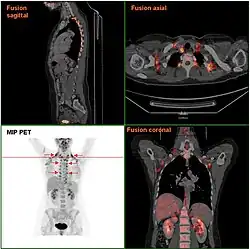

Chez l'être humain, la chaleur corporelle est contrôlée pour maintenir une température corporelle autour de 37 ℃. La glande responsable de sa régulation est le tronc cérébral, et en particulier la région thermostatique de l’hypothalamus[2]. Pendant les périodes de repos, elle est produite majoritairement par le cœur, le foie, le cerveau, les reins et les organes endocriniens. Par contre, pendant l'exercice physique, elle provient surtout de la contraction des muscles squelettiques, qui produisent une énergie plusieurs fois supérieure à celle du reste des organes[4]. Le sang qui circule par ces organes contribue à distribuer cette énergie par tout le corps.

Quand la température corporelle descend, à cause d'un environnement froid, par exemple, les muscles squelettiques se contractent (stimulés par les neurones moteurs contrôlés par l'hypothalamus), produisant des mouvements involontaires au rythme de 10 à 20 par seconde, connus sous le nom de tremblements[5]. Comme aucun travail extérieur n'est généré, les tremblements sont assez efficaces dans la production de chaleur. À part les variations d'activité musculaire, le contrôle hormonal est la deuxième voie interne principale de régulation des émissions de chaleur corporelle[5]. L'accumulation de cette chaleur pourrait être influencée par la fatigue[6].

Chez certains animaux endothermes[7], la graisse brune est un tissu spécialisé en la génération de chaleur corporelle, de manière alternative aux tremblements. Dans ses mitochondries, la fonction respiratoire est découplée de la production d'ATP, et ce grâce à l'enzyme thermogénine. Pour les nouveau-nés humains, ce tissu adipeux peut supposer jusqu'à 5 % du poids corporel. De cette manière, les bébés arrivent à conserver leur chaleur sans avoir à frissonner, ce qu'ils ne peuvent pas faire parce que leur système nerveux n'est pas suffisamment développé[8]. Dans les humains adultes, ce tissu tend à disparaître, mais peut persister sous certaines conditions[9].